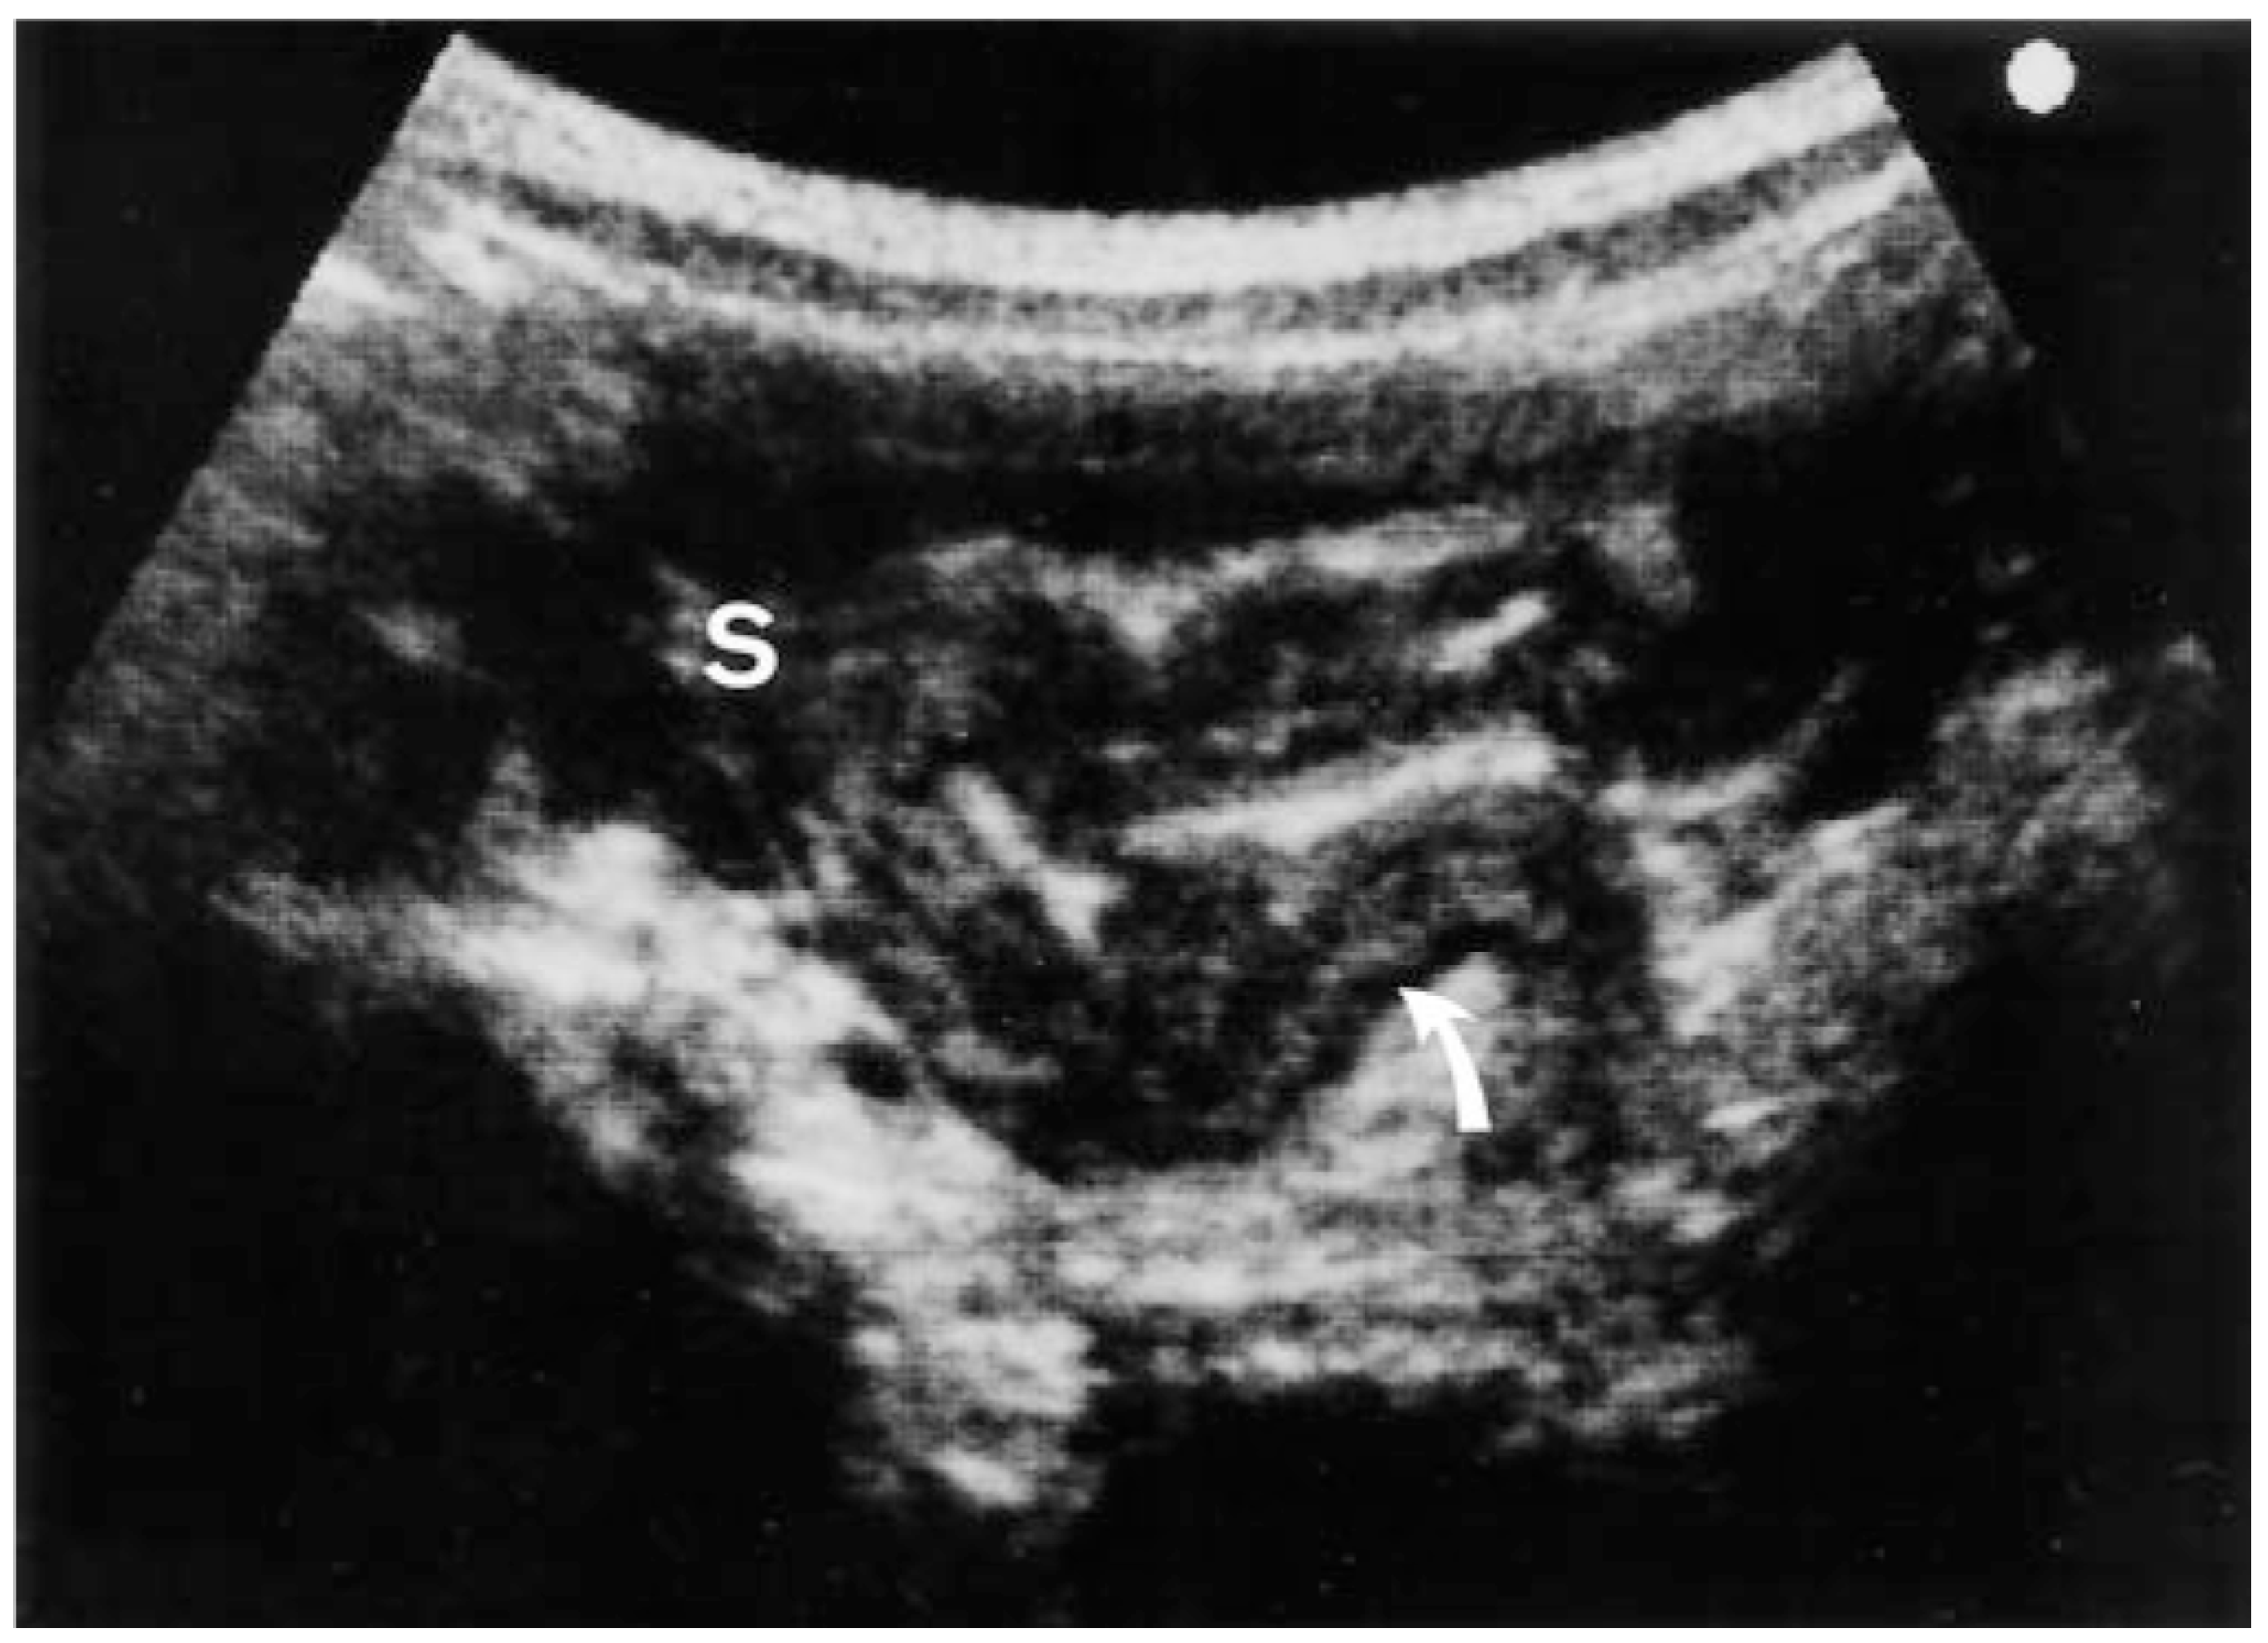

3.1.3. Ultrasonography

3.1.4. Magnetic Resonance Imaging